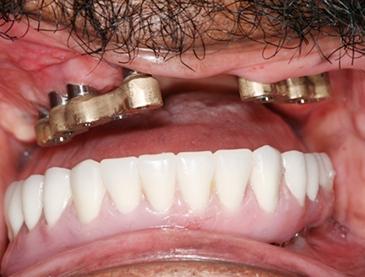

Fully edentulous clinical cases